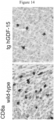

- Figure 6 shows exemplary tissue sections from melanoma brain metastases having high no (upper panel) or high (lower panel) GDF-15 immunoreactivity, which were stained by immunohistochemistry for GDF-15 and for the T-cell marker proteins CD3 and CD8, respectively, as indicated in the Figure.

- the numerous infiltrating immune cells are seen as dark spots.

- the scarce infiltrating immune cells are depicted by arrows (CD3 and CD8-positive cells are indicated by arrows).